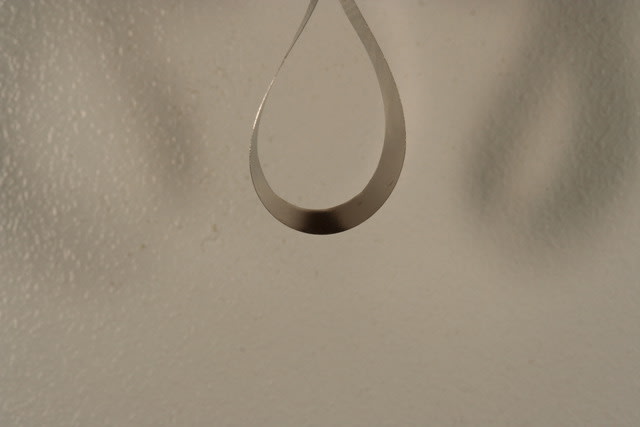

L’idée est de matricer la dent, et pour ça d’utiliser une matrice banane (greater curve), souvent découpée à moitié largeur pour pouvoir rester sous la ligne de plus grand contour de la dent et bien glisser en sous gingival en serrant la matrice autour de la dent.

Matrice banane 1 u7nw5s - Eugenol

l'intérêt de la matrice banane est que repliée dans le porte matrice (cf troisième photo) elle est plus serrée d'un coté que de l'autre, et du coup, si on est sous la ligne de plus grand contour de la dent (d'ou l'intérêt de la découper en deux) on peut en serrant descendre loin sous la gencive et bien sertir en cervical